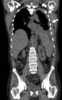

Pleural mesothelioma

Mesothelioma is a type of cancer that develops from the thin layer of tissue that covers many of the internal organs (known as the mesothelium). The most common area affected is the lining of the lungs and chest wall. [Source: Wikipedia ]